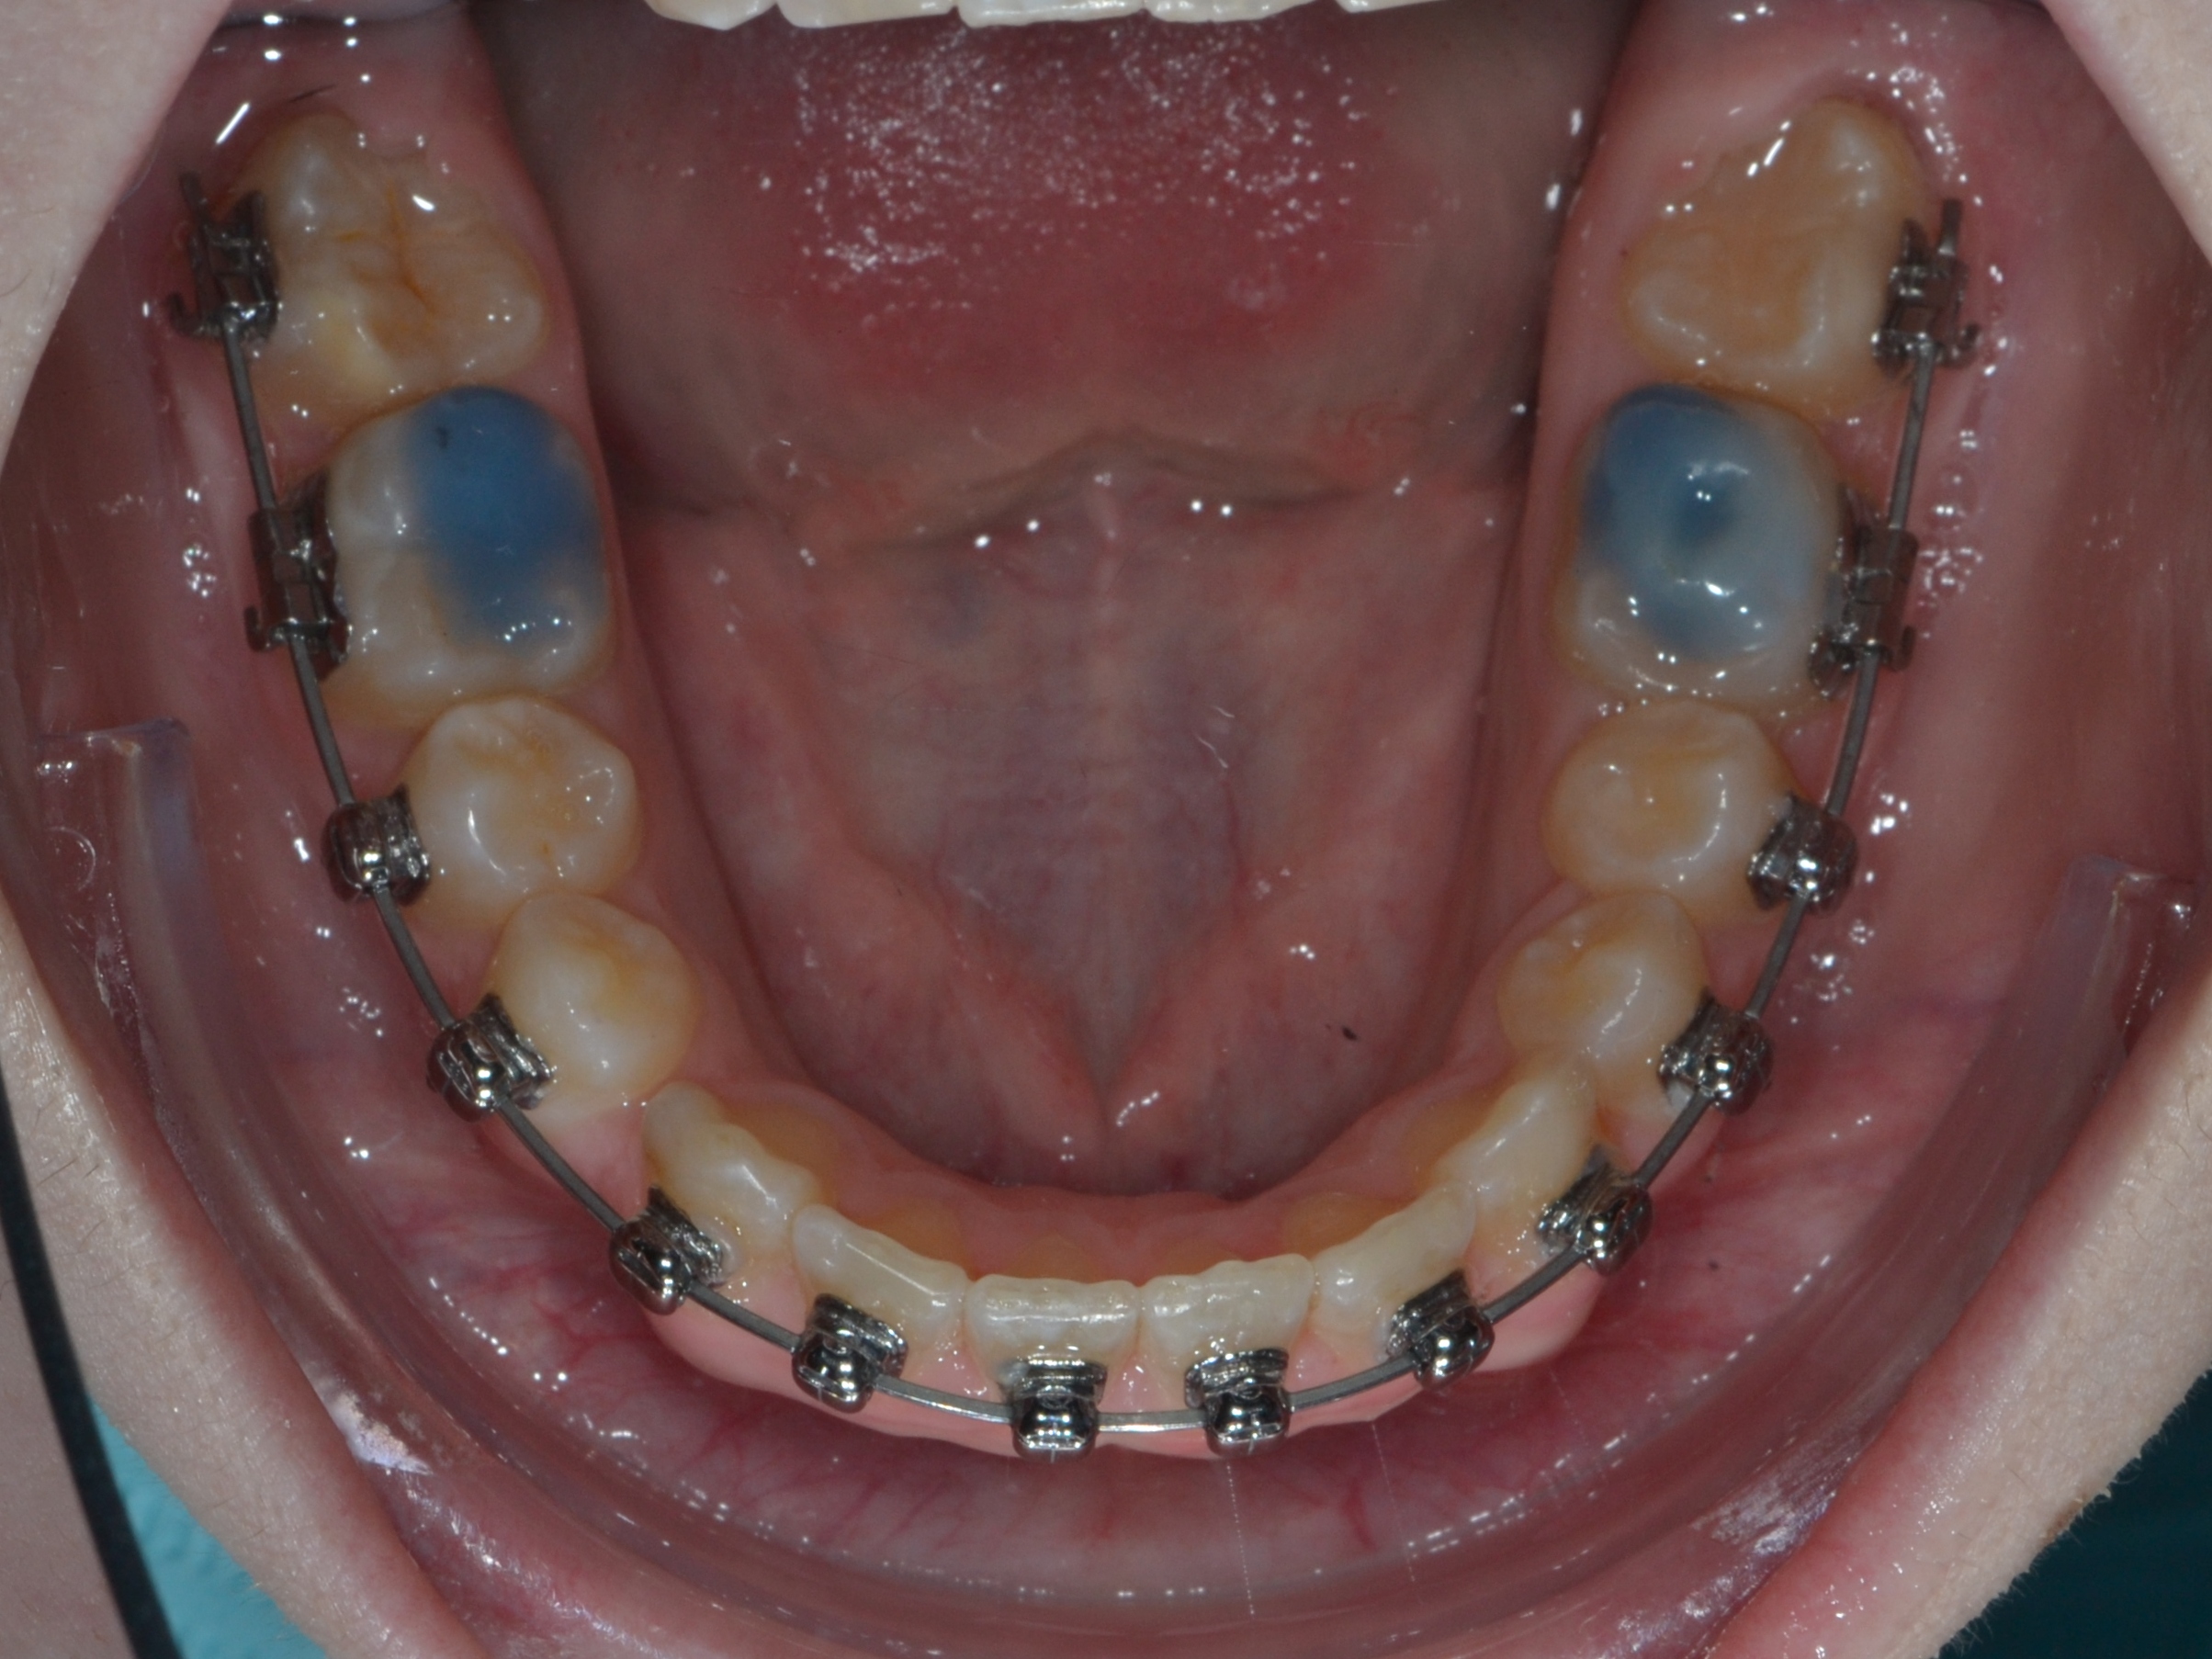

1

До фиксации

Июль 2024 г.